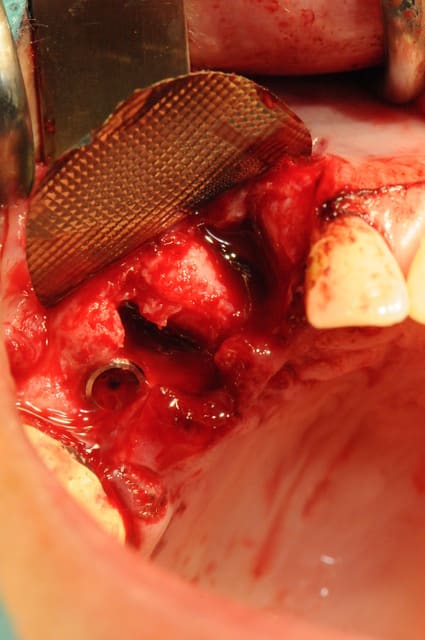

ici , fracture 13-14:

rog avec membrane titane

correction esthétique du niveau des collets de 12 et 11 (forte égression originel de 13-12-11 par rapport au secteur 2)